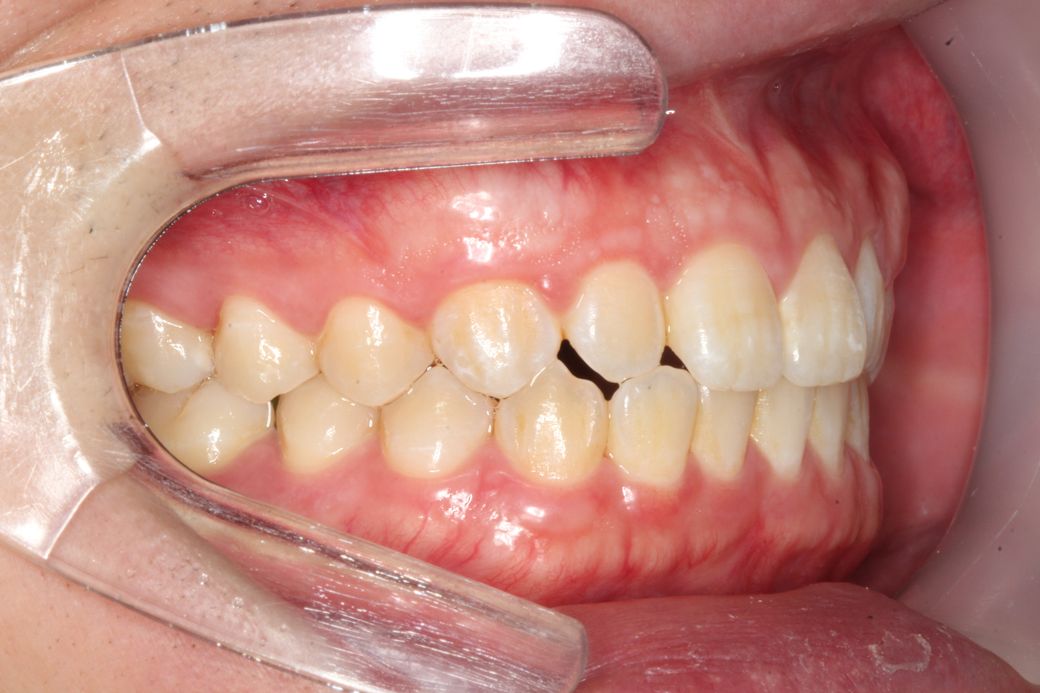

치과에서 사진찍었는데 사진을 보니 잇몸이 돌출된 느낌이 들어서요 치아 각도는 정상같아 보이는데 잇몸이 전체적으로 앞으로 쏠린느낌이 듭니다

• 1번 째 사진